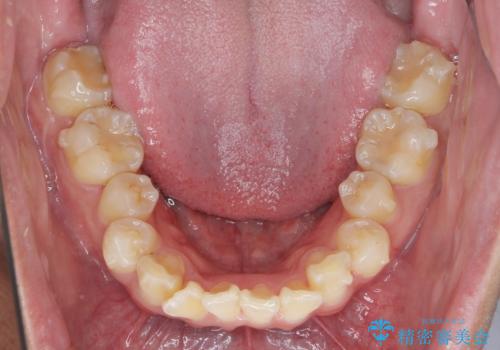

遠心移動を伴うマウスピース非抜歯矯正治療

- 「前歯の見た目を改善したい。」と矯正治療を希望され来院されました。

前歯のガタつきに加え、上顎が前にある咬合関係(上顎前突)を改善すべく、マイクロインプラントを用いた上顎奥歯の後方移動、拡大、ディスキングを用いたマウスピース矯正治療を計画します。

マイクロインプラントを使用したことで、しっかりと遠心移動が為され、良好な咬合関係が達成されました。